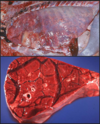

Q

This is a picture of a rumen. What lesion is shown here?

A

Acute, multifocal to coalescing ulcerative ruminitis